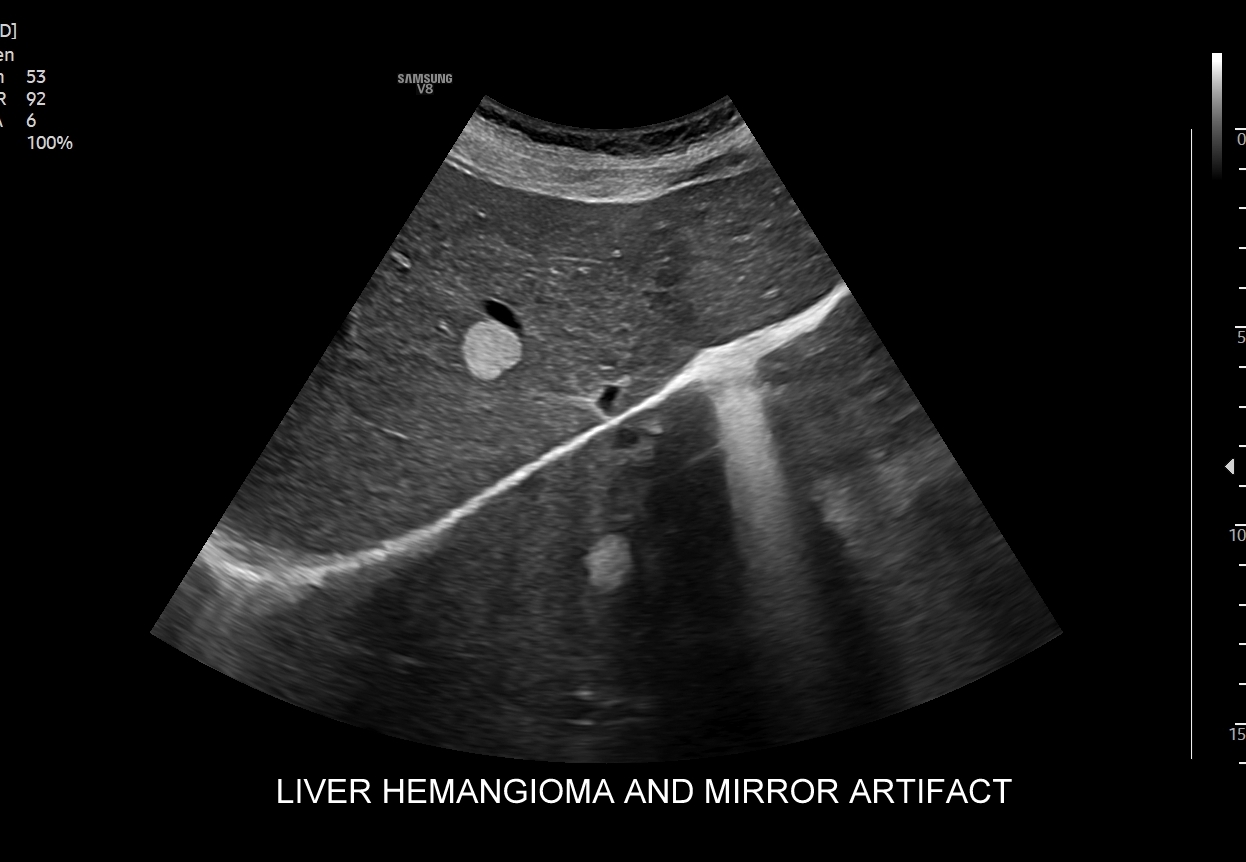

- Klasyczne badanie USG narządów jamy brzusznej.

- Elastografia wątroby.

Multiparametryczne badanie USG (MPUS) jest rozwinięciem klasycznego USG jamy brzusznej zwykle w formie jednoczasowego zastosowania różnorodnych technologicznie trybów obrazowania USG, zarówno tzw. „nowych”, jak i „starych”. Wśród nowych najważniejszym jest obrazowanie mikrounaczynienia (MVI / MVF), a w dalszej kolejności tryby elastograficzne oraz metody ilościowej oceny stłuszczenia wątroby. Wymienione „nowe” modalności w połączeniu ze „starymi”, przede wszystkim z Dopplerem spektralnym i color-Dopplerem, stanowią rdzeń nowoczesnej ultrasonografii MPUS, gdyż umożliwiają pozyskanie znacznie większej ilości informacji z badania USG w porównywalnym przedziale czasowym, a przez to uzyskanie jego większej wartości diagnostycznej. Przykładowo badanie MPUS umożliwia różnicowanie pseudoguzów od guzów prawdziwych, ocenę żywotności tkanek, biologii nowotworów, funkcjonalną ocenę nerek i wątroby, poprawia obrazowanie dużych naczyń krwionośnych oraz charakterystykę podejrzanych torbieli.